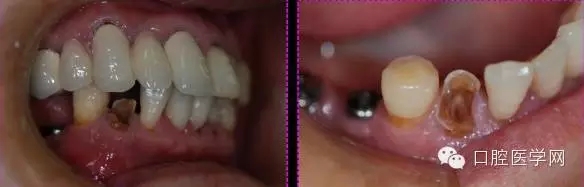

術(shù)前病例記錄

這個(gè)是到我這邊的牙合面照片

根管口沒(méi)有完全展開(kāi),我用8#Kfile疏通了下不是非常順暢,患者疼痛有可能是因?yàn)橹癒file疏通的時(shí)候根尖有被激惹,或者是根管物有被退出根尖孔。

檢查:叩痛(+++)

我重新用8#和10#Kfile疏通,發(fā)現(xiàn)根管有滲出物